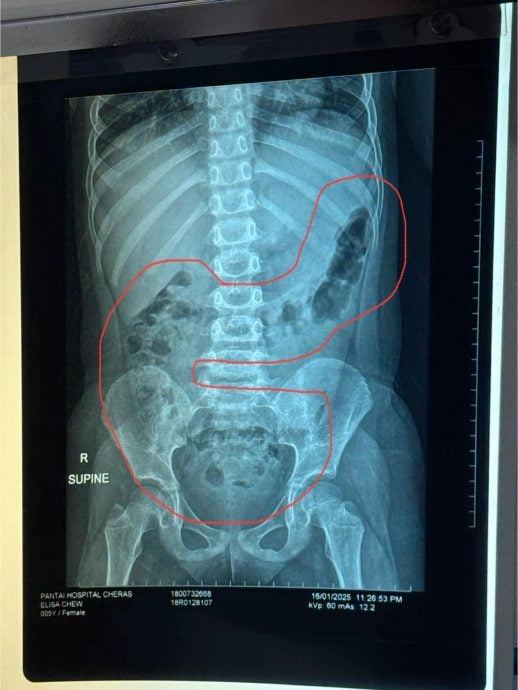

一名来自吉隆坡的母亲周四凌晨在脸书发文,题为“给不吃青菜的娃看看”、“便便顶到肺”,贴文附上一张儿童X光照片,瞬间吸引许多网民关注和转发。

女童在照了X光以后,腹痛的原因终于真相大白,事实如老医生所料——她的5岁女儿腹部内累积的大便,多到顶到了肺部的位置,“难怪肚子一直痛”。